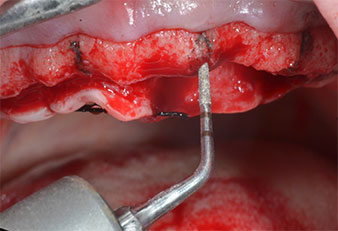

Пиезоелектрически инструмент с диамантено покритие с форма на пламък (Piezomed I1) e използван за маркиране на позициите на имплантите и за пилотна подготовка (Фиг. 3). Препарацията беше извършена с внимателни вертикални движения, с намалена мощност, пълна иригация и лек натиск (под 300 g) След това се приложи пилотен инструмент (Piezomed I2A/ I2P) за първоначално увеличение на диаметъра на имплантното ложе с 2 mm (Фиг. 4), последвано от 3 mm разширение (Фиг. 5)

В настоящия случай инструменти Z25P и Z35P не са използвани поради сравнително меката задна кост, която лесно се обработва с I3A/I3P.

Поради сравнително твърдата кост (D2) в тази област, 10-милиметровото имплантно ложе в позиции 11 и 21 беше завършено с ротационен дрил с диаметър 4 mm в комбинация с W&H хирургичен обратен наконечник WS-75 L, W&H имплантологичен мотор Implantmed и опционалния W&H Osstell ISQ модул. За разлика от това, благодарение на меката кост, дисталните зони се подготвят до окончателен диаметър 3 mm, използвайки накрайник за Piezomed I3P. Имплантите най-накрая са поставени трансгингивално, за да остеоинтегрират за три месеца (Фиг. 6-10). Съществуващата протеза се фиксира на четирите временни импланта (Фиг. 8).